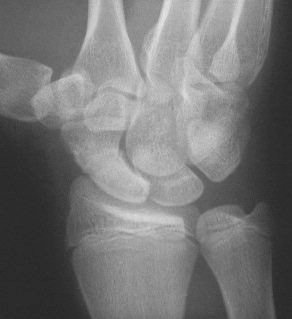

Clinical Example: Scaphoid fracture with total avascular necrosis similar to Preiser's disease

One of the problems with scaphoid fractures is ischemia of the proximal fracture fragment resulting in delayed union, nonunion or irretrievable avascular necrosis. In this case, ischemic changes involving the entire scaphoid are documented following a scaphoid fracture due to minimal trauma. This progressed with cystic changes and AVN on MRI. The patient had persistent pronounced wrist stiffness and pain. As pointed out to me by Dr. Lawrence Schneider (thanks!), this is technically not true Preiser's, for the fracture preceded the AVN.